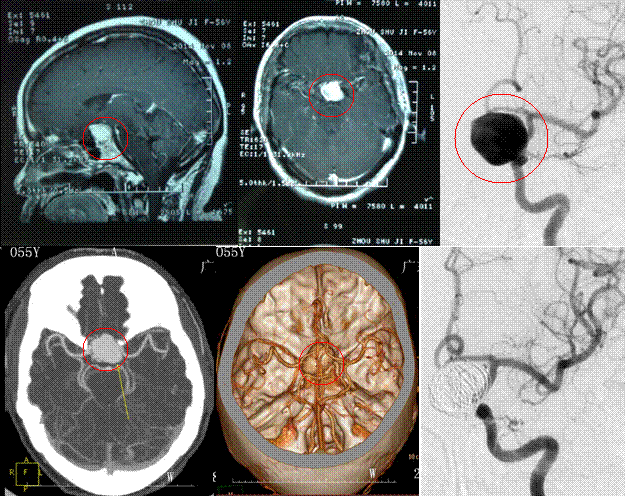

患者两月前无明显诱因出现头痛,伴有头晕,头痛呈阵发性,主要位于前额部,偶尔伴有麻木感,休息后可自行缓解。就诊当地医院检查头颅MRT,结果:鞍区占位性病变,考虑垂体瘤可能性大,建议患者行经鼻蝶垂体瘤切除术,患者为进一步治疗,以“鞍区占位性病变,考虑垂体瘤可能性大”收治入院。

检查:CTA提示:鞍区巨大动脉瘤;完善相关检查后,在全麻下为患者行“鞍区巨大动脉瘤栓塞术”,现患者神志清楚,未诉头晕头痛,查体未见明显异常。

手术前后检查对比